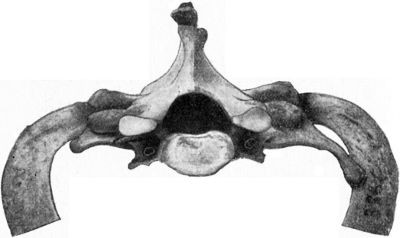

29 12.Os Innominatum showing new Socket formed after Old-standing Dislocation

41 13.Oblique Fracture of Right Clavicle in Middle Third, united